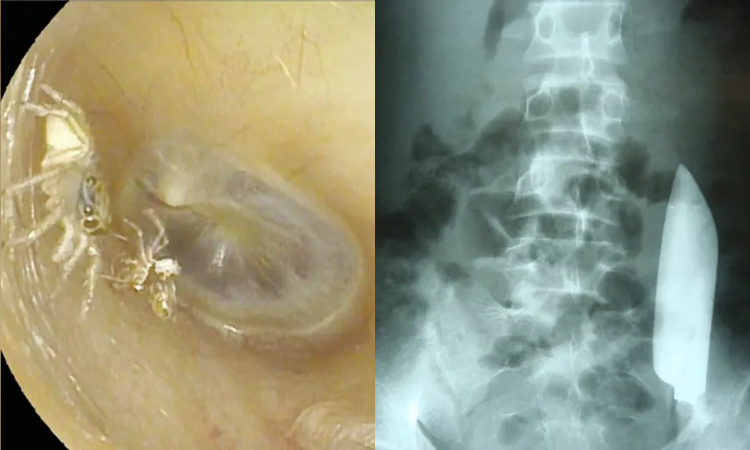

Laba-laba yang hidup di telinga seorang wanita (kiri) dan bilah pisau yang berada di perut seorang pria (kanan). (Live Science)

2. Laba-laba ditemukan dalam telinga seorang wanita

Seorang wanita di Taiwan mendengar suara gemeresik aneh yang keluar dari telinganya selama empat hari. Ia tidak menduga suara itu berasal dari seekor laba-laba sepanjang 0,1 inci (0,25 cm) yang merayap di telinga kirinya, di samping kerang luarnya (exoskeleton) yang keras dan telah berganti kulit.

6. Bilah pisau ‘mengambang’ di sisi lain perut seorang pria